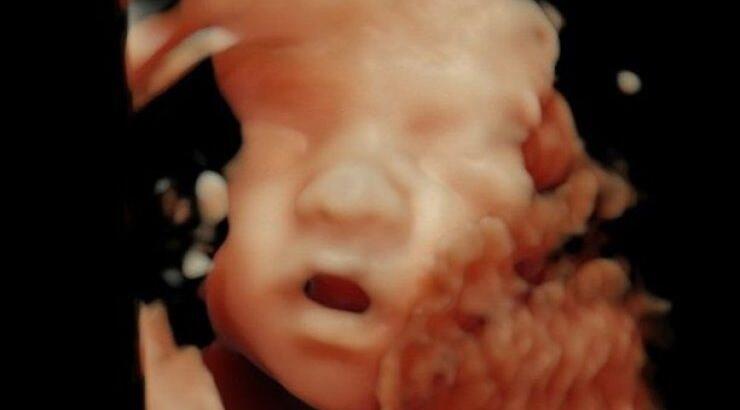

Chiara Ferragni: Μας έδειξε για πρώτη φορά το πρόσωπο του νεογέννητου γιου…